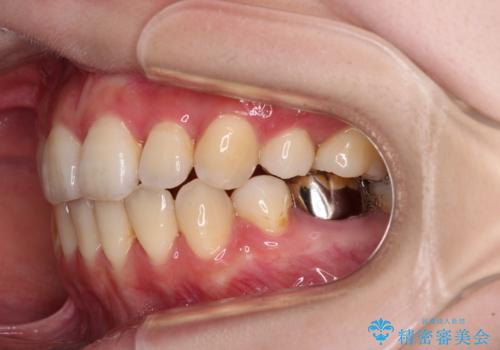

- ハーフリンガル

- 口元の突出感を気にして来院された患者様です。

上下左右の第一小臼歯4本を抜歯して口元を下げる治療計画としました。

裏側矯正特有の抜歯スペースに前後の歯が倒れ込む状態が長く続き、改善に長期間を要しました。